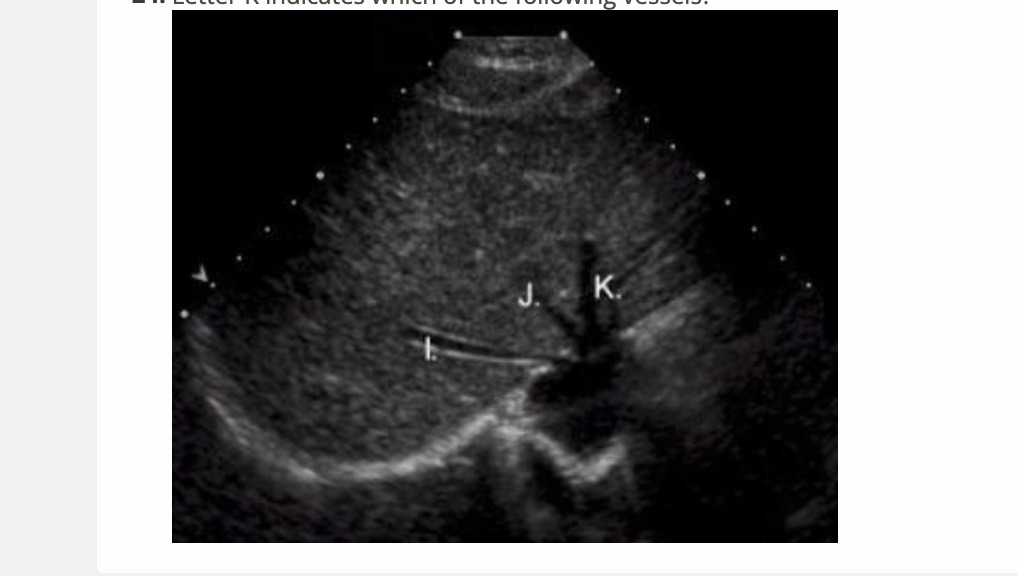

letter K is which vessel

.

a) left portal vein

b) right portal vein

c) middle hepatic vein

d) left hepatic vein

d. left hepatic vein

letter I is which vessel

b) right hepatic vein

b. right hepatic vein